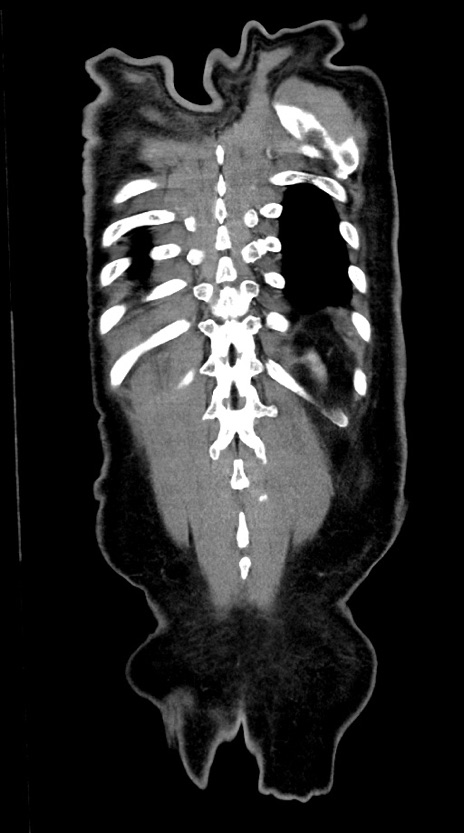

横断像